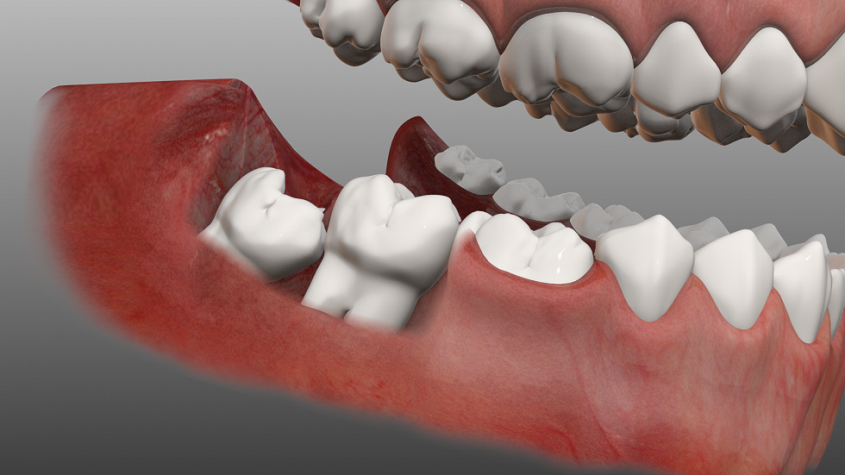

Зубы слева